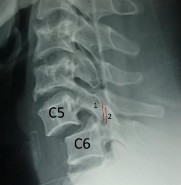

Hình 1.24: Bong gân nặng C5-C6, có đủ năm tiêu chuẩn của René Louis : số 1 là khoảng cách hai mỏm gai tăng bất thường; số 2 là mặt khớp dưới của C5 không song song với mặt khớp C6; số 3 là lộ mặt khớp trên của C6 >50%; số 4 là góc hai cao nguyên sống >100 ; số 5 là trượt C5 ra trước.

X-quang ngang thấy gù ít, giãn các mỏm gai ít, thân đốt sống trượt ra trước nhiều # 5-6mm hoặc 50% thân đốt. X-quang thẳng khoảng cách 2 mỏm gai giãn ít và nằm trên đường thẳng. X-quang chéo thấy mỏm khớp dưới của đốt sống trên nằm trước mỏm khớp trên của đốt sống dưới. X-quang động không nên làm.

Hình 1.26: Trật 2 mỏm khớp: 1-mỏm khớp trên của C6 nằm sau, 2-mỏm khớp dưới của C5 nằm trước.